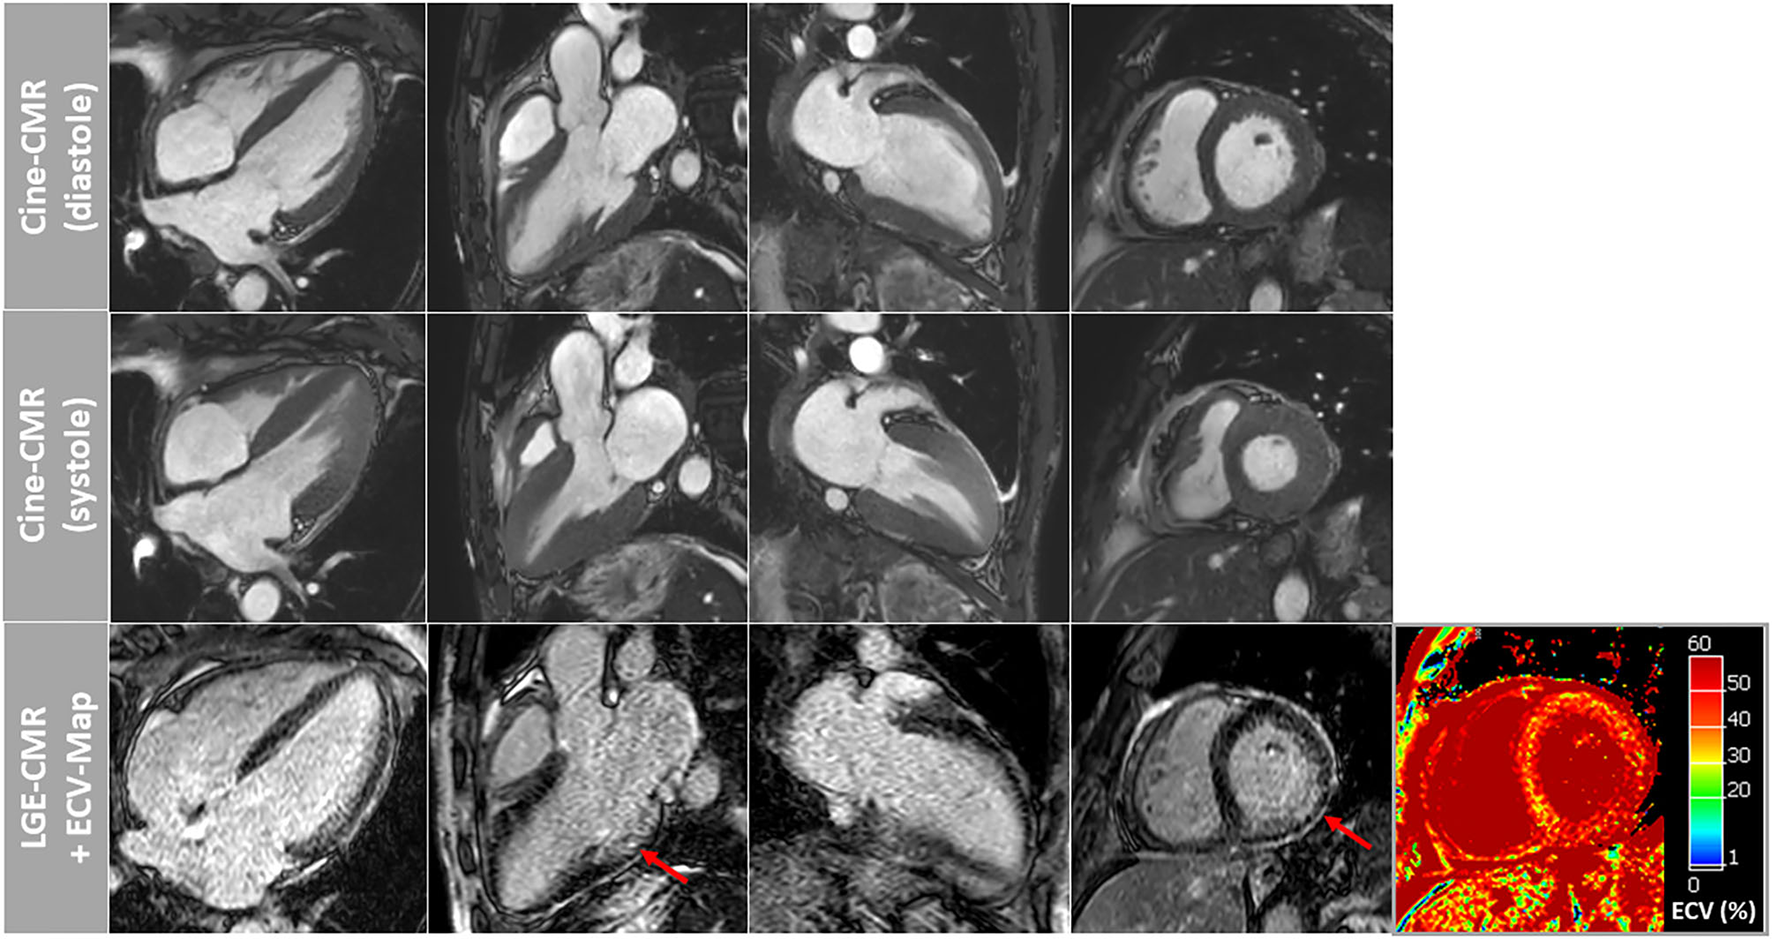

Both patients showed similar results regarding cine-imaging: LVs were slightly dilated, mild to moderately hypertrophied with preserved systolic function. Right ventricles (RV) showed no abnormalities with regard to size and function. Regarding myocardial tissue characterization, a subtle and rather diffuse pattern of LGE was detected in the basal segments of the LV lateral wall. Moreover, a little pericardial effusion was observed (Figure 1A). Patient 2 showed a slightly more pronounced non-ischemic pattern of LGE in the basal to midventricular inferior/inferolateral segments of the LV wall (Figure 2). In addition, some pericardial enhancement suggestive of pericarditis as well as pleural effusion suggestive of poly-serositis, most likely in the setting of the underlying disease, were present. Importantly, myocardial mapping measurements resulted in a marked elevation of ECV-values as well as slight elevation of native T1-values predominantly in the basal septal and lateral LV walls, and rather normal T2-values in both patients—indicating a rather chronic, non-inflammatory and most likely infiltrative process (Figures 1A, 2). Detailed mapping results are illustrated in Table 1.

Figure 2

Cardiovascular magnetic resonance (CMR) images of patient-2 showing cine images in diastole and systole as well as corresponding late-gadolinium-enhancement (LGE) and extracellular volume fraction (ECV) maps of the myocardium. A slightly more pronounced non-ischemic pattern of LGE was observed in this patient in the basal to midventricular inferior/inferolateral segments of the LV wall (red arrows). Again, ECV maps illustrated highly elevated myocardial ECV values in the septal and lateral wall segments.